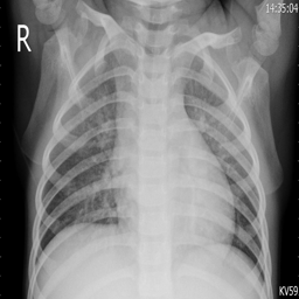

To test how good our proposed method is, we used chest X-rays of COVID19 patients, healthy patients, patients with opaque lungs, and patients with viral pneumonia. We collected images from two publicly available data sets.

COVID19 X-ray database dataset [14] [19]. This was created by a team of researchers from various universities, in cooperation with doctors from Malaysia. They examined various X-rays and classified them into COVID-19, Viral Pneumonia, Lung Opacity and Healthy chest X-rays.

COVID-19 image from the COVID19 X-ray database[14] [19] was originally around 3500. We upsampled it to 7,000 by using various image augmentation techniques. We then took equal samples of images from Viral Pneumonia, Lung Opacity and Healthy chest X-rays for the Non-COVID class.

III-B Dataset Preprocessing

The COVID-19 images are up-sampled using image augmentation techniques with the help of albumentations [13] library. The chest X-ray is flipped vertically or horizontally, then randomly rotated to the limit of 270 degrees with constant edges, and the brightness and contrast are arbitrarily adjusted to the limit of 0.4.

chest X-rays are of different sizes from 447 × 530 to 4200 × 3290 pixels. Therefore, we made the target size of images as 224 x 244 pixels. As the models were pretrained on RGB images, we created fake RGB images by stacking the channel over itself. Contrast Limited Adaptive Histogram Equalization (CLAHE) [13] is used as an image enhancement method. CLAHE is a revision of Adaptive Histogram Equalization (AHE) that avoids excessive contrast enhancement in the image.

The COVID-19 viral infection is a global pandemic and is rapidly mutating. The lungs of the infected people are inflamed due to this viral infection. Hence, examining chest X-rays is one of the possible approaches in the detection of COVID-19. In this study, we have proposed an automated and accurate technique for distinguishing COVID-19 cases from Viral Pneumonia, Lung Opacity, and Healthy chest X-rays. We experimented with four different transfer learning-based architectures and, their performance is evaluated based on four performance metrics. The results of ViT-B/32[18] confirm that transformer-based models are on par with professional radiologists.